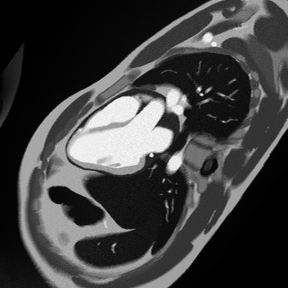

✅ Correct Planning for 3-Chamber Early Enhancement:

Correct Planning for 3-Chamber Sequence, early and late enhancement

✅ Correct Planning for 3-Chamber Late Enhancement (same as early 3-chamber):

✅ 3-Chamber Early Gadolinium Enhancement – Correct Image Example:

3-Chamber Early Gadolinium Enhancement – Correct Image Example

Things to Look for in 3-Chamber Early Enhancement:

• Check the septum and inferior wall for MVO

• Ensure the aortic outflow tract is visible

• Compare with late enhancement to track MVO evolution